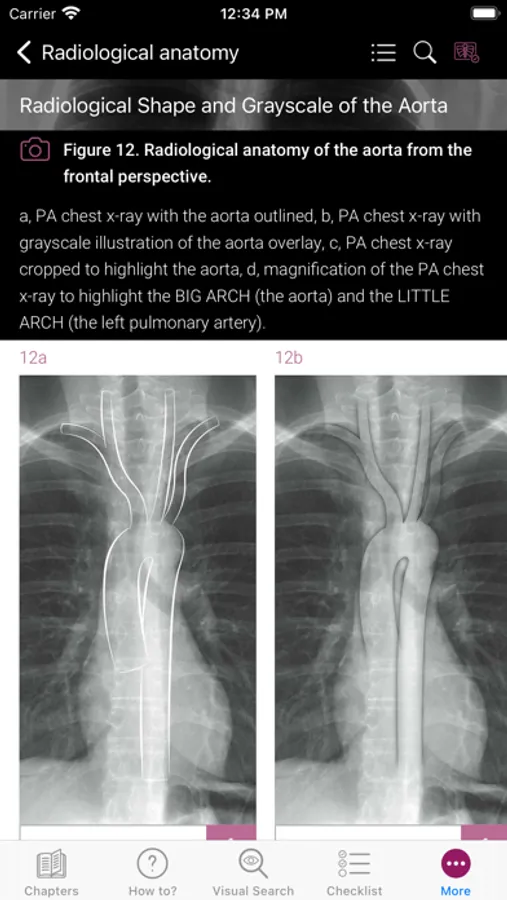

Radiological Anatomy – Descriptions of various anatomical structures as they would appear on PA and lateral chest x-rays.